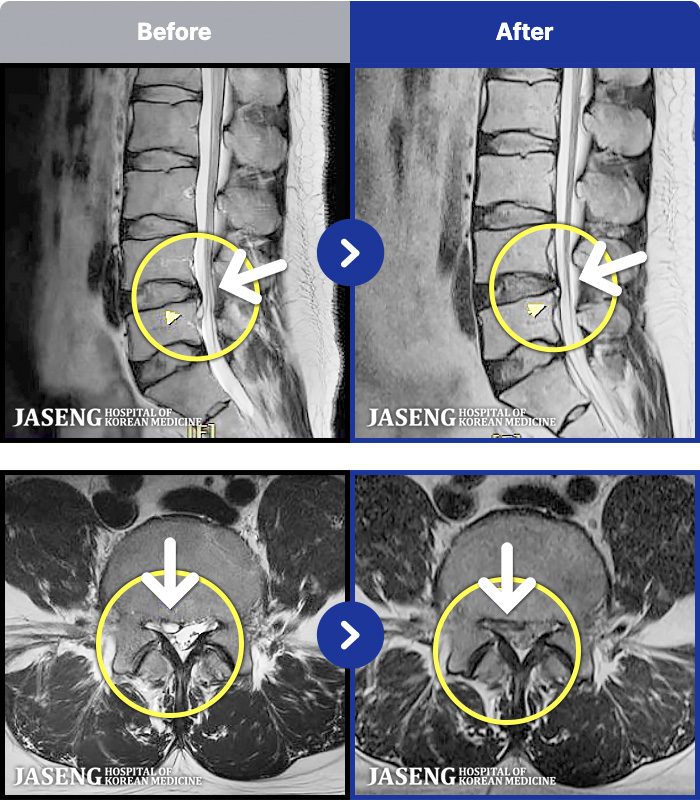

95 MRI ũ ʸ Ȯϼ.